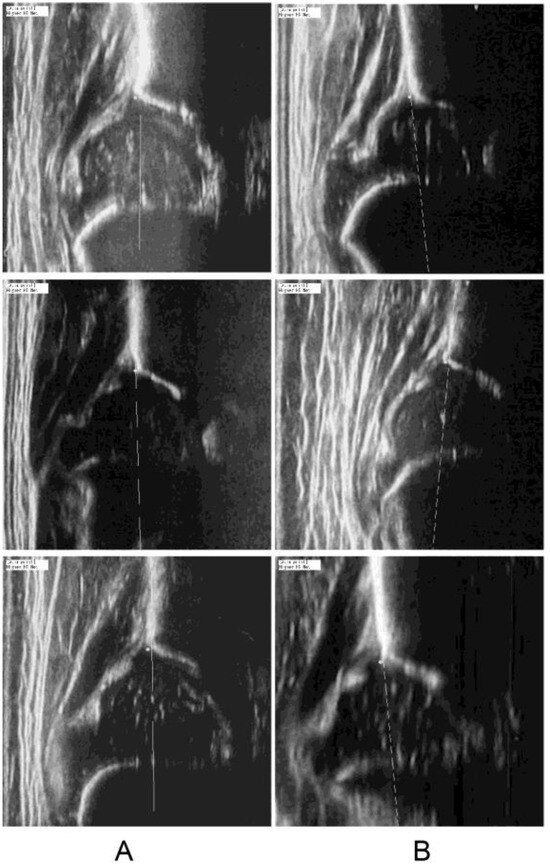

2.3.2. Quality Assessment Through Signal Heterogeneity Analysis

2.3.3. Generation of the Alpha Angle